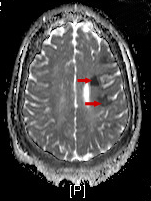

Findings of an MRI scan of the head were significant for multifocal bilateral subacute infarcts, predominantly scattered throughout the left cerebral hemisphere with superimposed multifocal remote infarcts, and vessel occlusion (Figures 1-3).

Figure 2. Diffusion-weighted MRI scan using apparent diffusion coefficient showing the infarcted tissue as acute/subacute, indicated by hypoechoic areas.